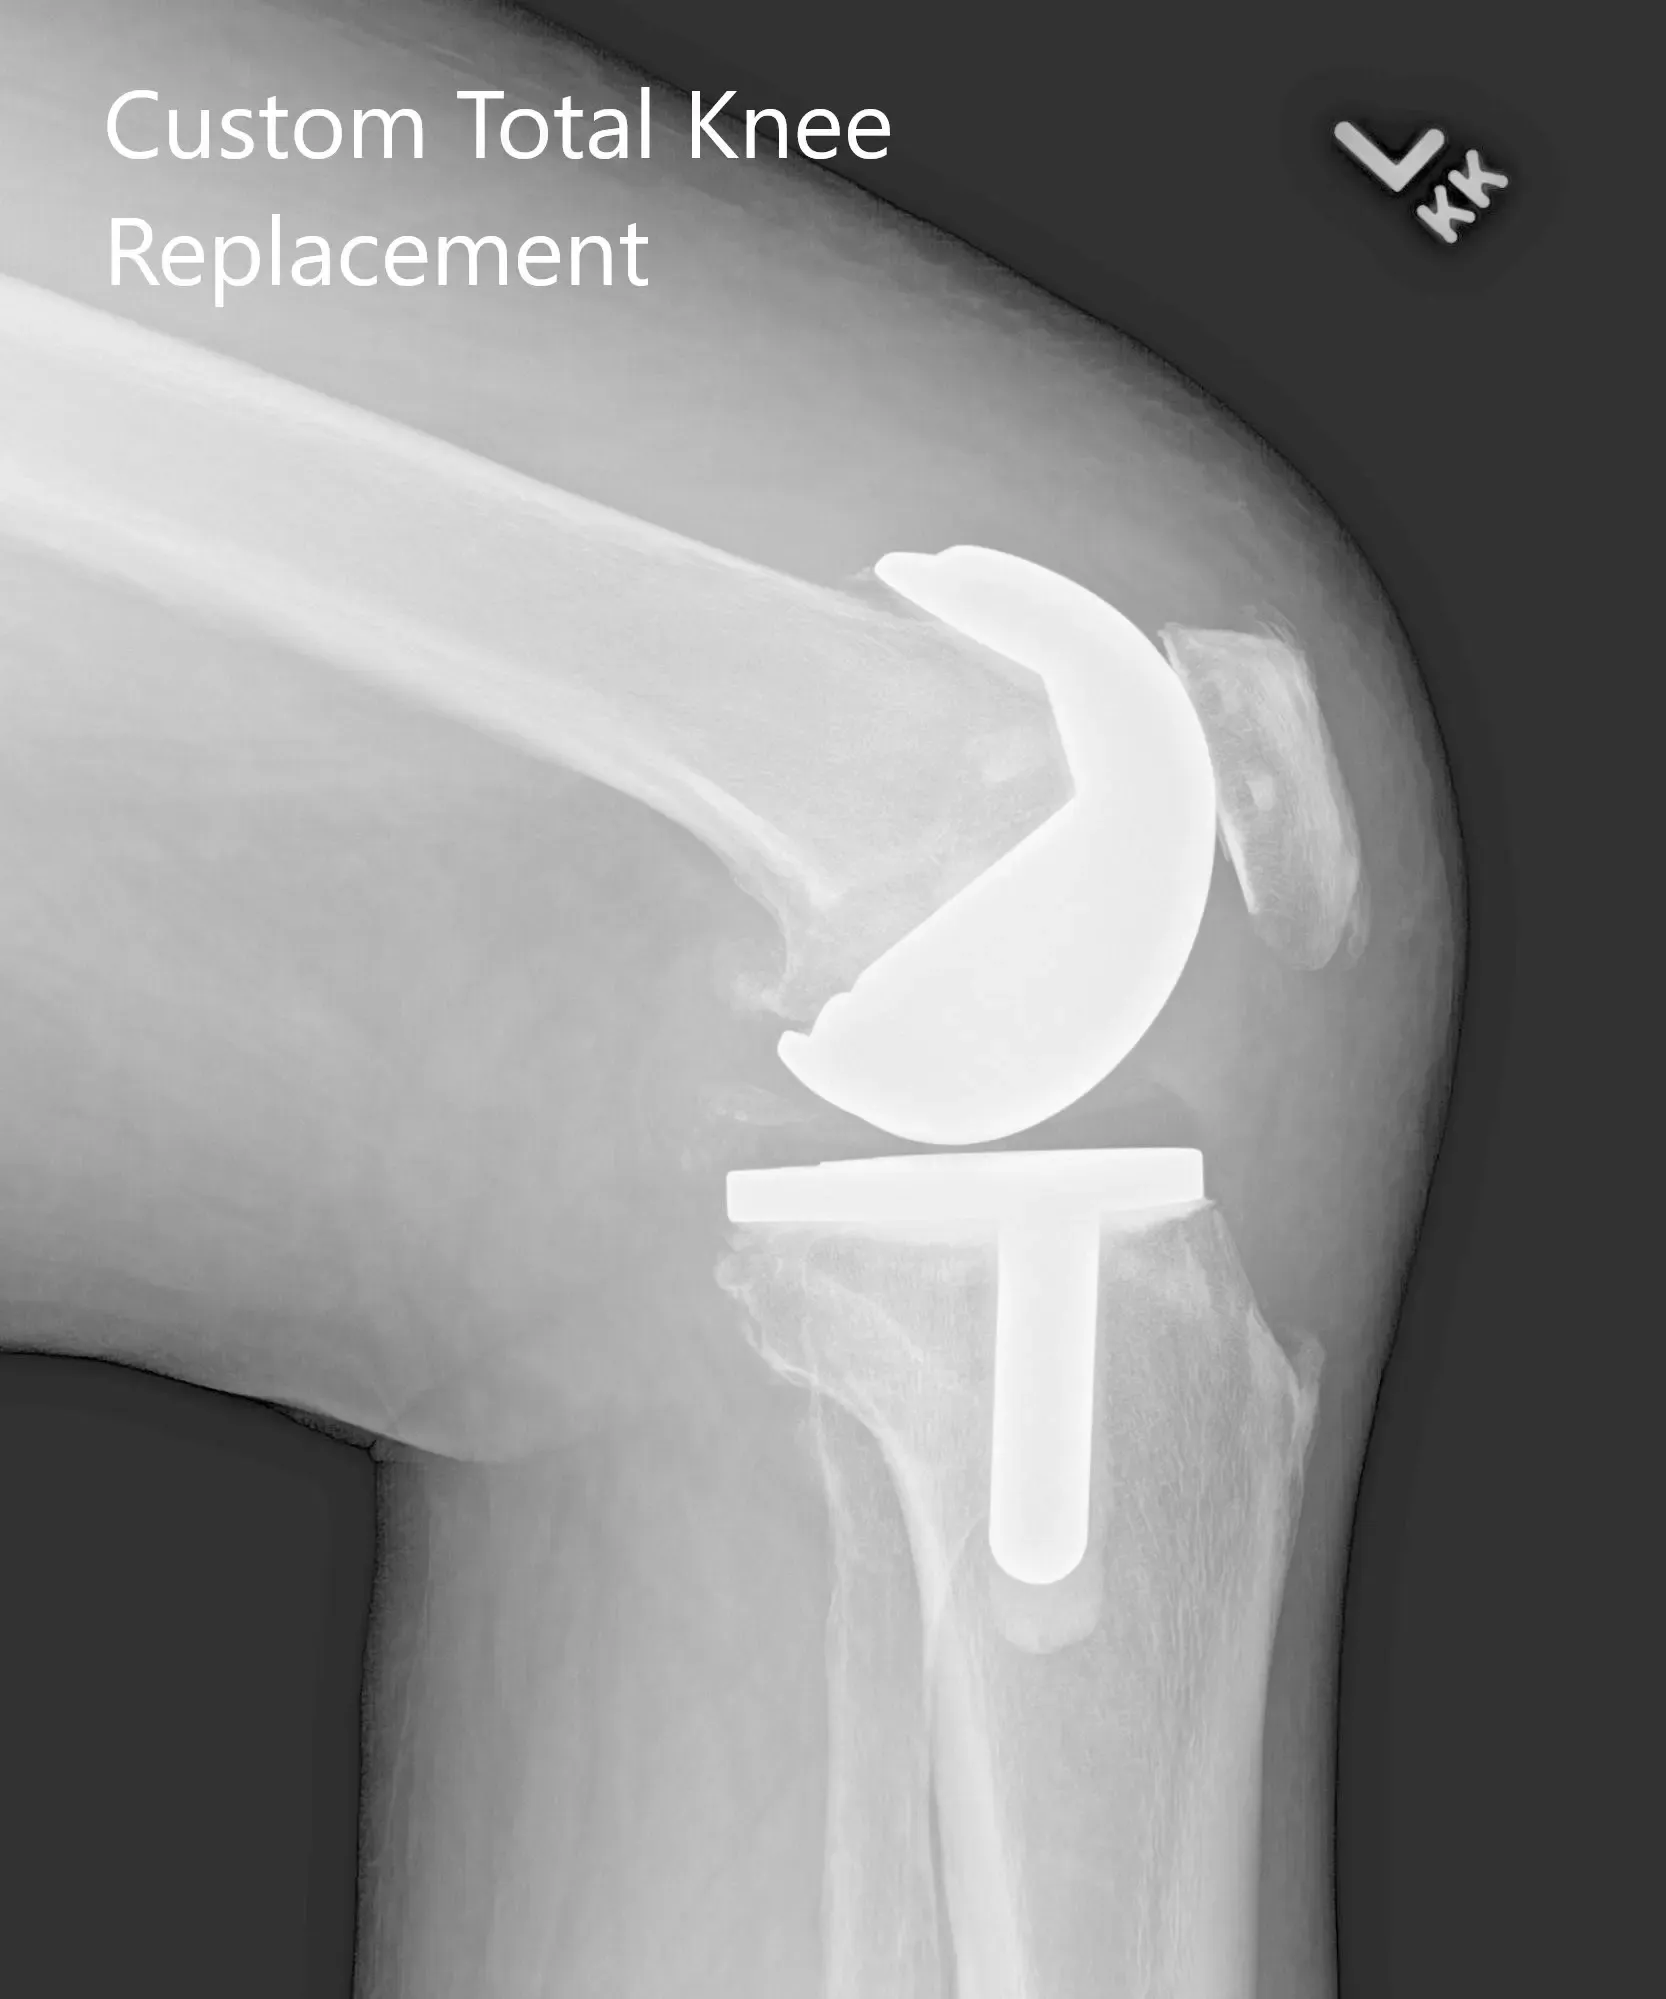

Postoperative X-ray showing AP and lateral images of the left knee.

Implants used: Custom femoral implant with 6 mm polyethylene insert with a custom tibial tray with a 38 mm patellar implant.